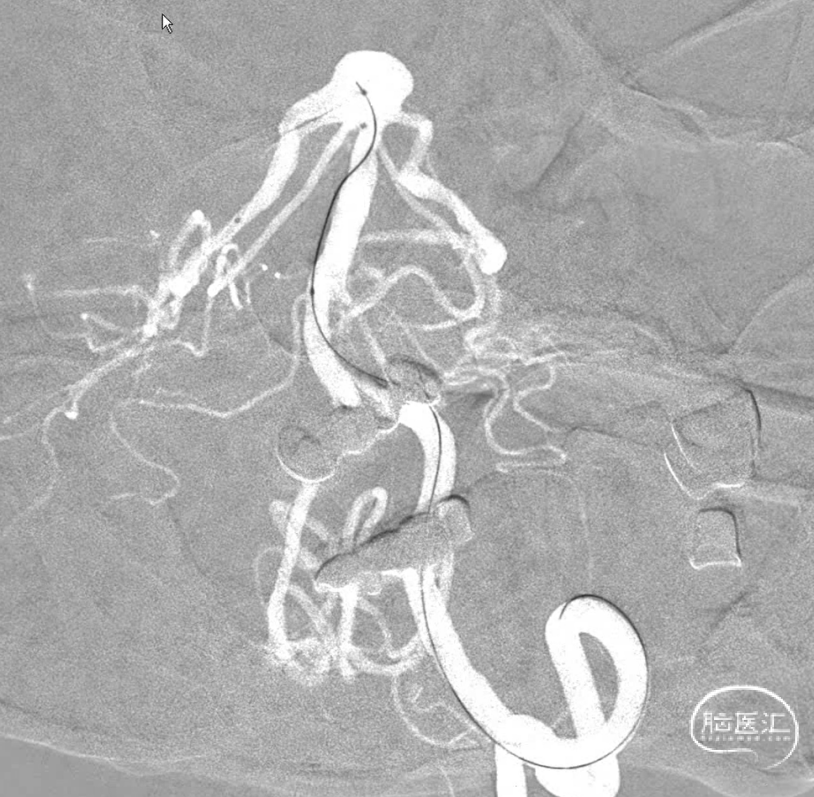

左侧为主椎,当然把6F导引导管放到左侧(黑色箭头),右侧椎稍微细一些,安排上5F的导引导管(红色箭头)。因此右侧大脑后的支架导管塑型角度稍大一些弧形,弹簧圈微导管安排S型,左侧嘛?单弯足以。

用的是可以利用弹簧圈微导管释放支架的导管。好处有:第一容易到位,即使到达大脑后动脉角度较大时也可以通过微导管塑型减少对动脉瘤的骚扰。第二支架在血管内形成血栓的概率小一些。

右侧大脑后动脉导管到位,解释一下由于远端血管条件不是太好,因此没有往更远走一些,二则,支架为无头的因此,此位置够用了。

因为在同侧所以也把弹簧圈微导管到位。虽然塑型角度比较大,可能由于血管的束缚和导管的回弹,角度感觉还是小了些,不过应该还是可以的。不过再上第三个管时,应该把前两个管锁紧。

第三管很容易到位,所有大神都已到位,那就开始干活吧。